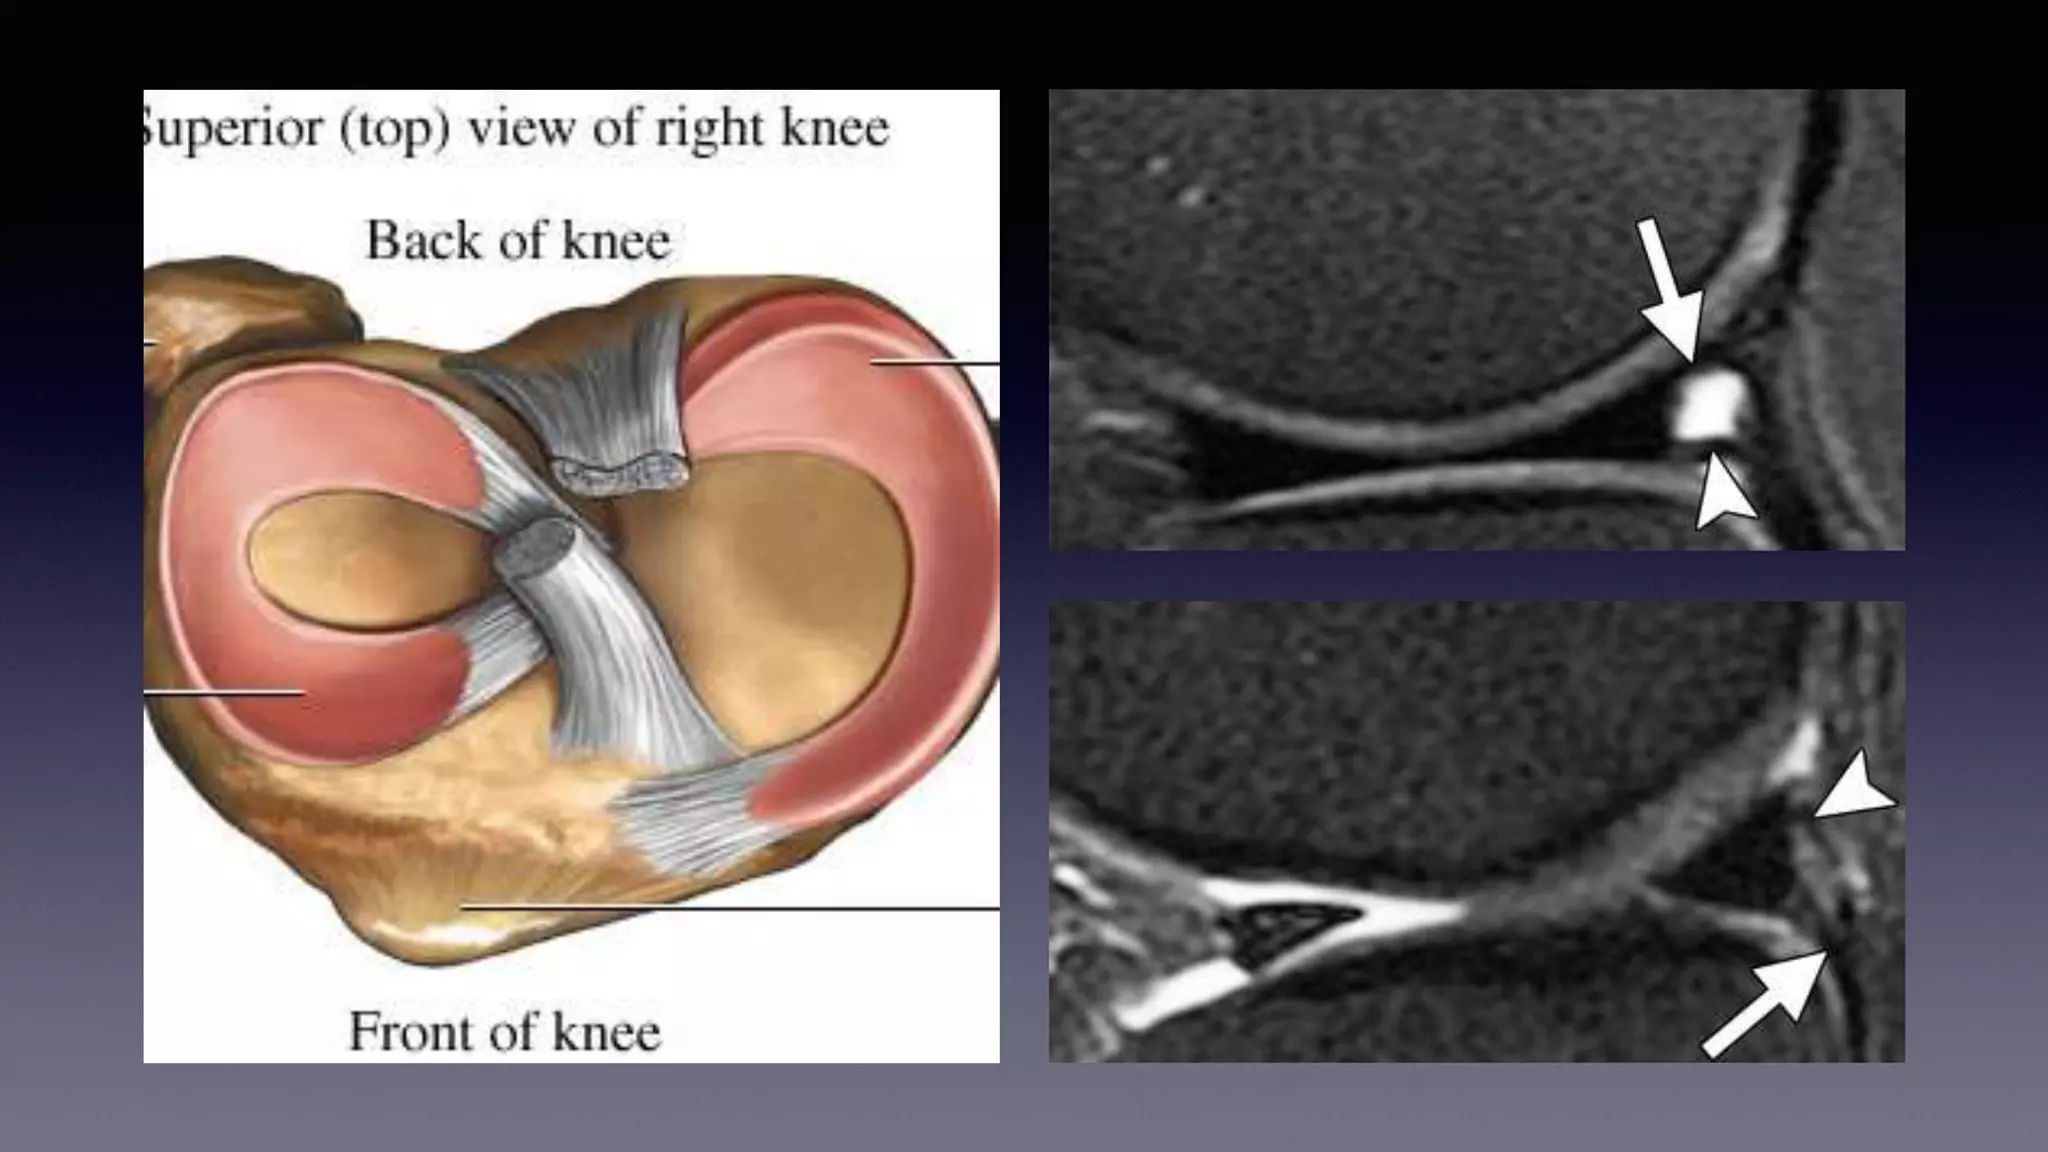

This document discusses using MRI to diagnose ligament injuries in the knee. It begins with an overview of MRI anatomy of the knee and expected pathology. It then discusses specific ligaments like the ACL, PCL, MCL and LCL. For the ACL, it shows images of acute tears, chronic tears and intrasubstance tears. It emphasizes knowing the knee anatomy well and correlating any abnormalities seen with clinical findings in order to apply the appropriate treatment.